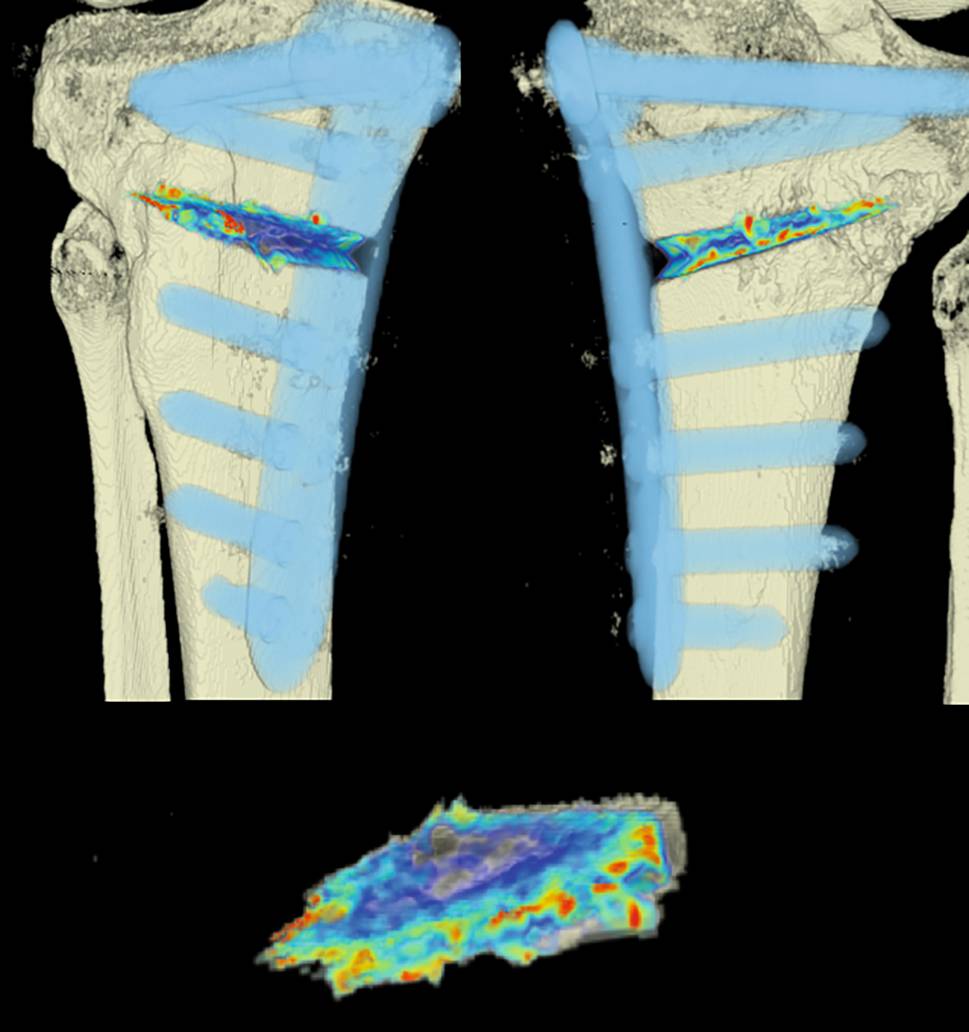

The areas with the greatest change of BMD representing the morphology of bone healing in the gap were visualized using color coding. Red zones mark the areas with most bone growth, green zones moderate bone growth and blue areas show only minimal changes in BMD (Fig. 7). Mean bone density in the osteotomy gap was significantly higher (p < 0.0002) 12 weeks postoperatively when compared to the baseline BMD calculated from the CT scans directly after the operation. The mean BMD at baseline was 54.586 mg/ccm (31.892–80.668) and increased to a mean BMD of 112.487 mg/ccm (58.141–178.214) at follow-up. The BMD increased in all patients except for one (Fig. 8 and Table 4).

Fig. 7

CT scan analysis included a visualization of the highest BMD changes: the gap is evenly filled with new bone; red zones mark the areas with most bone growth, green zones moderate bone growth and blue areas show only minimal changes in BMD

Mean BMD measurement values in Hounsfield units (HU) at baseline and follow-up; p < 0.0002. Visualization of changes in BMD for each patient are displayed using color coding (red = high bone growth, green = moderate bone growth, blue = low bone growth)

Visualization of BMD changes

With the help of the CT scan data, a computerized program was able to quantify the ossification of the gap. This is the first study to use an objective method for quantification of ossification in the osteotomy gap after HTO. Surprisingly, the morphology of bone healing was not as expected and described in literature [2, 3]. When comparing the CT scans to the radiographs, the radiographs suggested that bone healing mostly happens at the lateral osteotomy gap and from there grows to the medial side of the gap. When analyzing the CT scans and marking the areas with the greatest changes of bone density, we were able to see that new bone was growing on all osteotomy surfaces evenly throughout the gap. With our semi-automatic computer program, it was possible to quantify new bone formation by measuring bone mineral density and its changes over time. To our knowledge, there is no existing comparable quantification system for analysis of gap healing in the literature.